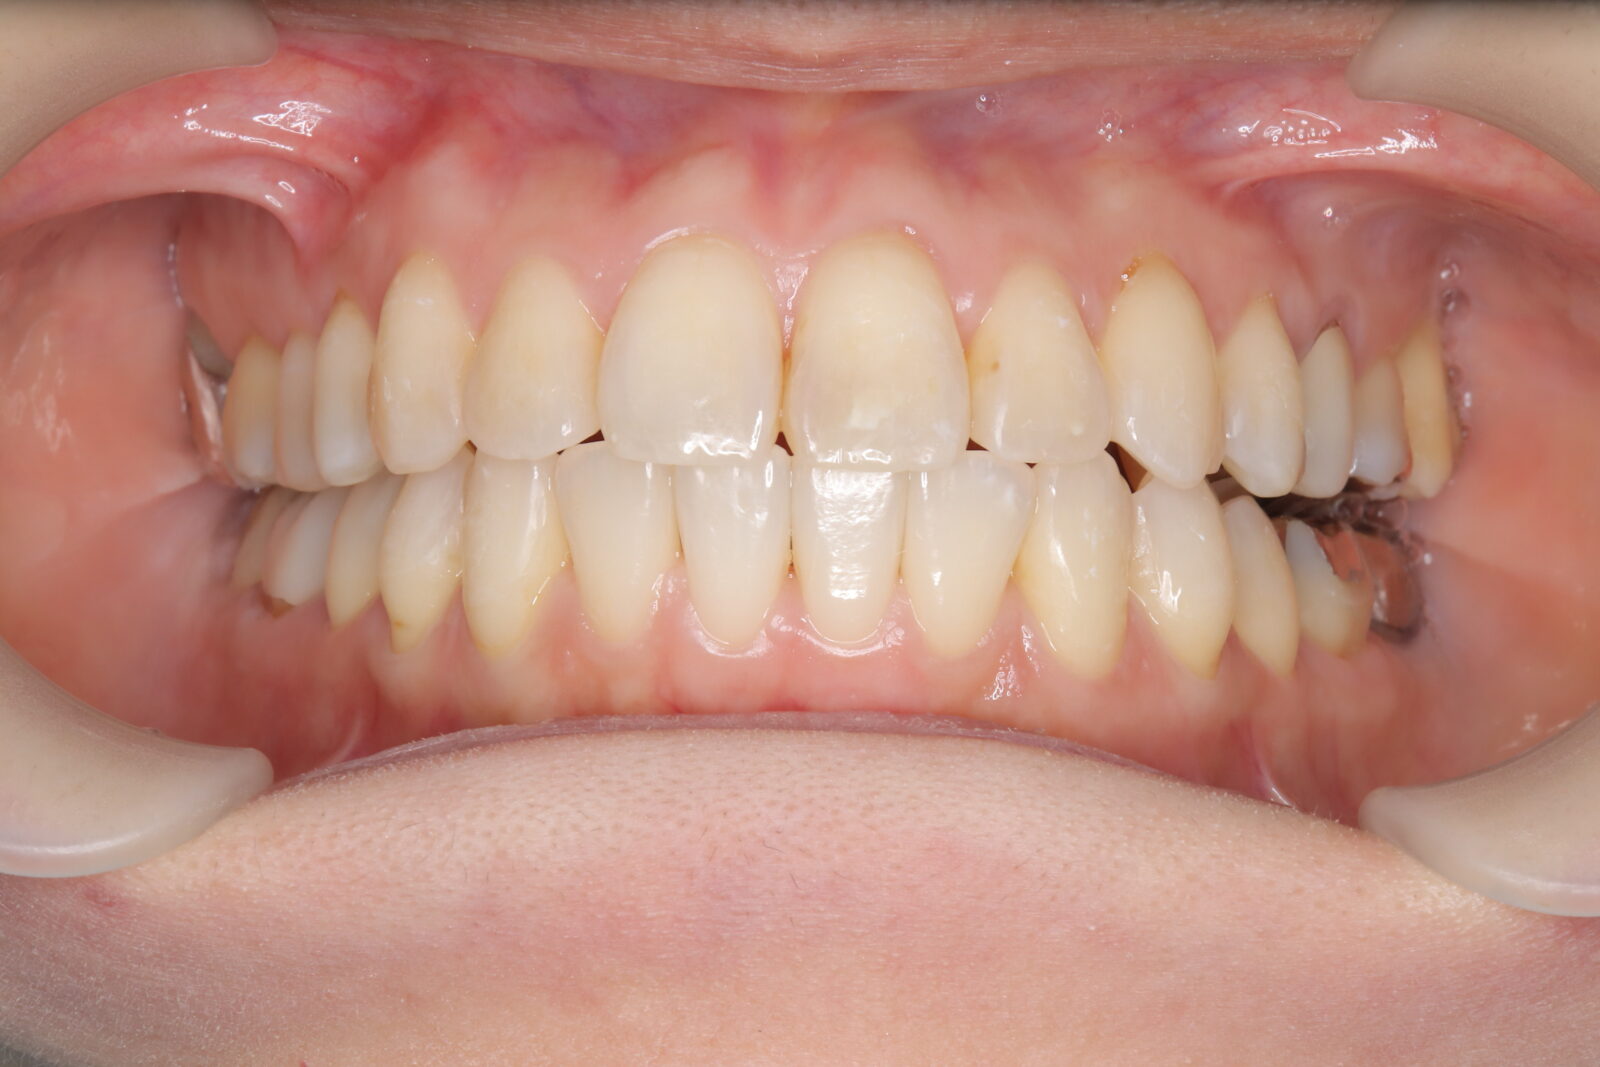

インビザライン(全体矯正)+ホワイトニングコースの症例

歯の裏に歯が隠れてしまっていたため、全体矯正(非抜歯+遠心移動)で美しく改善。

・費用:935,000円(税込)

・治療期間:30ヶ月

・通院回数:30回

・35歳女性

-リスクと副作用-

・長時間マウスピースを装着するため、むし歯や歯周病のリスクがある。治療後はリテーナーを装着しないと後戻りしてしまうリスクがある。

・ホワイトニング剤の影響で知覚過敏が起こる可能性がある。色が徐々に戻る可能性がる。